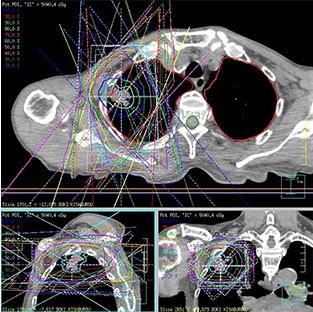

高水準の放射線治療

東京大学医学部附属病院と連携し、同水準の治療を推進近年のがん治療に欠かせなくなった放射線療法。川崎幸病院では、東京大学医学部附属病院のもと、同水準の放射線治療を行っています。また、新緑脳神経外科は、第7回世界サイバーナイフユーザー会(07年)において、治療実績で世界1位になったこともあり、高水準の治療を提供しています。

近年のがん治療に欠かせなくなった放射線療法。川崎幸病院では、東京大学医学部附属病院のもと、同水準の放射線治療を行っています。また、新緑脳神経外科は、第7回世界サイバーナイフユーザー会(07年)において、治療実績で世界1位になったこともあり、高水準の治療を提供しています。